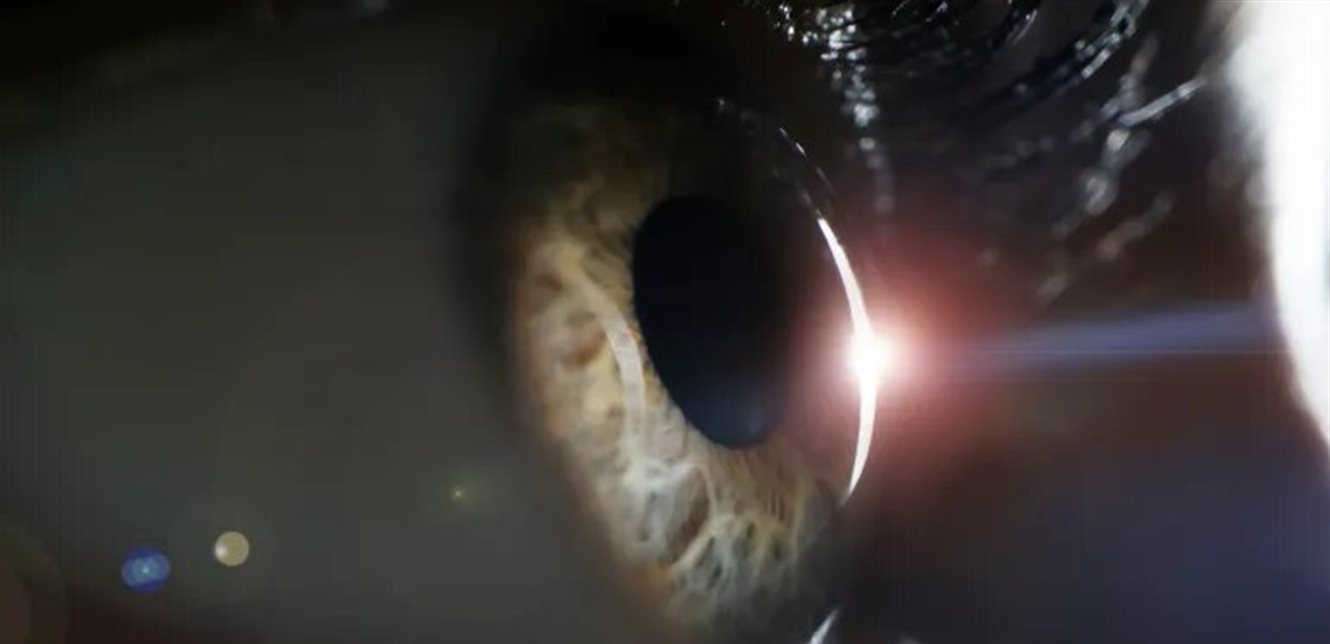

وأشارت الدراسة إلى أن مرض “الجلوكوما” أو الماء الأزرق يتصدر قائمة هذه الأمراض، حيث يتسبب في تلف العصب البصري تدريجياً دون أن يشعر المريض بأي أعراض في المراحل الأولى. كما حذرت من “اعتلال الشبكية السكري” الذي يهدد الملايين، حيث تبدأ الإصابة بنزيف بسيط أو تورم في الشبكية لا يؤثر على الرؤية فوراً، لكنه يمهد لفقدان البصر الكلي إذا أُهمل العلاج.

وتطرقت التقارير إلى “التنكس البقعي” المرتبط بالتقدم في السن، والذي يهاجم الرؤية المركزية الضرورية للقراءة والقيادة، مشددة على أن الكثيرين يخلطون بين أعراضه وبين ضعف النظر الطبيعي الناتج عن الشيخوخة، مما يضيع فرصة التدخل الطبي المبكر.

وشدد أطباء العيون على ضرورة إجراء فحص دوري وشامل للعين مرة واحدة سنوياً على الأقل، خاصة لمن تجاوزوا سن الأربعين أو يعانون من أمراض مزمنة مثل السكري وضغط الدم. وأكد الخبراء أن العديد من حالات فقدان البصر كان يمكن تلافيها بنسبة 90% لو تم تشخيصها في مراحلها “الصامتة”.